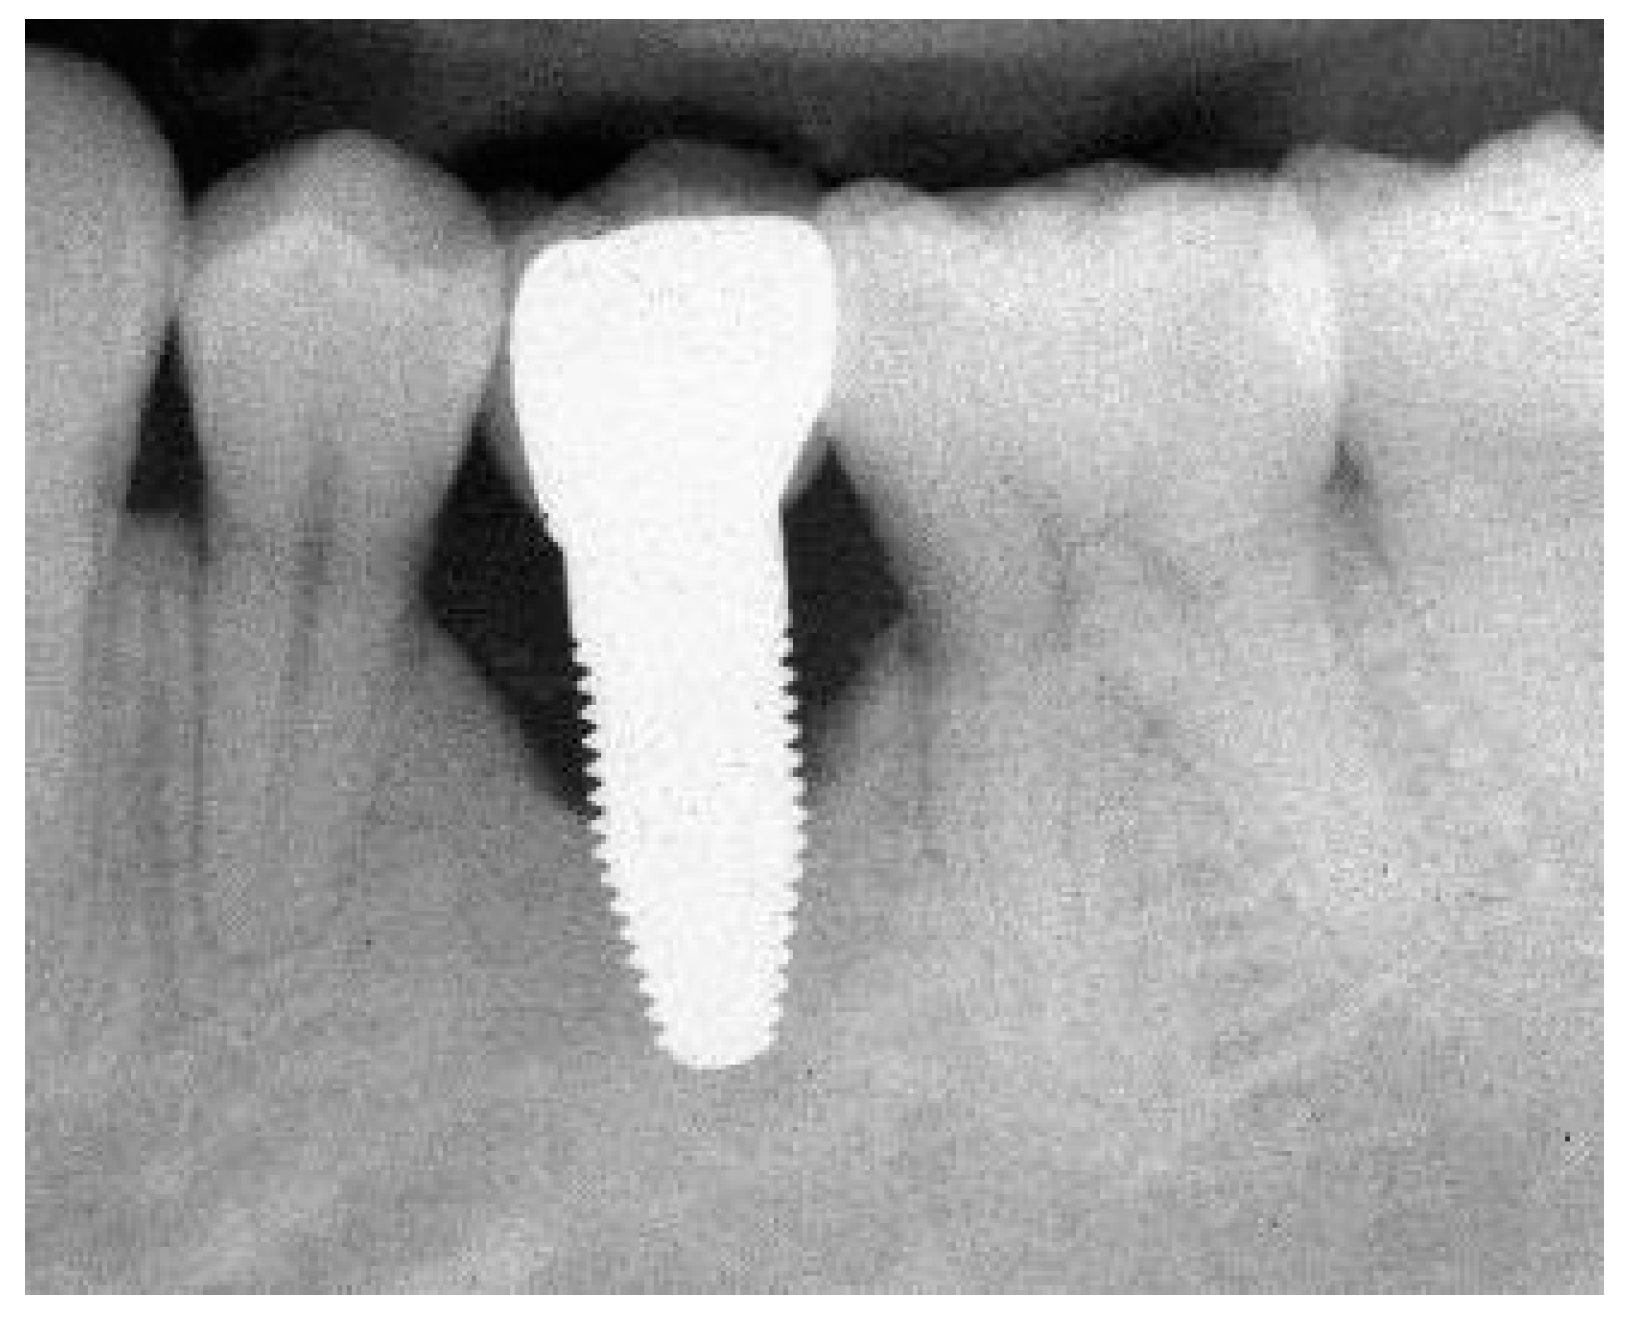

Figure 1.

(a) Exemplary radiograph at the 5-year follow-up depicting a single-tooth implant with a distinct vertical defect at the mesial and distal aspect of the implant. The lower corner of the straight cylindrical implant part was used as reference point for bone level calculations. (b) Clinical situation of the same implant prior to removal.

3.3. Marginal Bone Remodelling

From implant insertion (II) to PI, the mean marginal bone loss was 1.13 mm and from II to the 1-year follow-up it was 1.31 mm. A bone loss of 1.45 mm between II and the 3-year follow-up and of 1.12 mm between II and the 5-year follow-up was found. The results indicate that there was a slight further increase in bone loss from the 1-year to the 3-year follow-up but a decrease in bone loss from the 3-year to the 5-year follow-up (Table 7). At the 5-year follow-up, at 11 of 41 eligible implants (27%), a marginal bone loss of more than 2 mm was detected. Of these 11 implants, 5 demonstrated more than 3 mm of bone loss. This resulted in a 73% success grade I and to 88% success grade II after 5 years [26]. An exemplary radiograph and clinical picture show the typical bone loss pattern (Figure 1). Regarding any influence or correlation of baseline parameters, the performed univariate analysis did not disclose any effect or correlation of these parameters onto the bone remodelling/loss from implant insertion to the 5-year follow-up (Table 8).